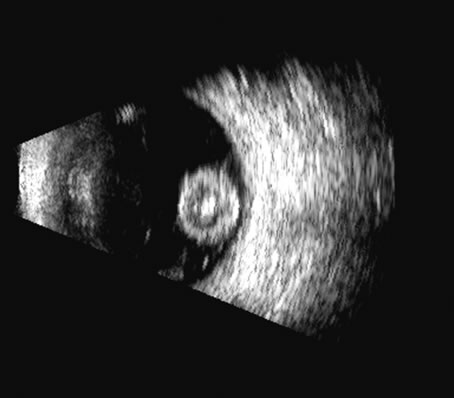

in the 50 MHz range for examining this region.5–7 Lens position, presence, and integrity can be shown most easily with immersion ultrasound, since the proximity of these structures to the transducer in contact techniques makes them difficult to display. Immersion or a water standoff makes it possible to visualize the anterior segment by moving the “noise” of the main bang of the transducer forward, away from the structures of interest and the focal zone onto this area.8 The lens is a “specular” reflector which, like the cornea, is a smooth, highly reflective surface. Whereas specular reflectors, such as the lens, may deflect most acoustic energy away from the transducer when insonified at an oblique angle, “diffuse” reflectors, such as blood-covered membranes, are more easily discerned on B-scan. Blood enhances lens boundaries; that is, it converts the specular reflective surface to a diffuse reflective surface, making the entire outline of the surface more easily seen, even at regions angled so they would otherwise deflect the returning echoes away from the transducer and not be identifiable. The posterior capsule is concave and thus perpendicular to the beam over much of the arc of sector B-scanning, thus making it always easy to identify. The lens outline should be smooth and unbroken (Fig. 1); a damaged lens often is cataractous and has internal echoes as well as interrupted surface echoes.9 Kinetic scanning, that is, real-time scanning while the patient moves his or her eye, can be used to check for mobility of the lens in dislocated or partially dislocated lenses. The four main areas of interest in the posterior chamber to the ocular surgeon are (1) iris and ciliary body tumors, (2) intraocular foreign bodies and trauma that may involve the lens, (3) intraocular lens placement and position that may cause irritation or decreased vision, and (4) hypotony with separation of the ciliary body from the sclera.10 Examples of a retroiridal cyst and a tumor are shown in Figures 2 and 3. Intraocular lens displacement, particularly erosion of haptics that may produce bleeding, is a commonly seen problem. An intraocular lens with a folded haptic is seen in Figure 4 and a retro displaced haptic is shown in Figure 5.